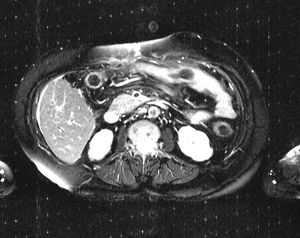

Zipper artifact

Zipper artifacts occur due to RF interference from electronic device in or near scanner room.